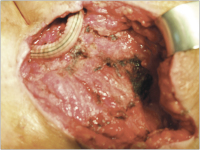

Prothese - Femur

Abbildung 1: Freiliegende femorofemorale Crossover-Prothese